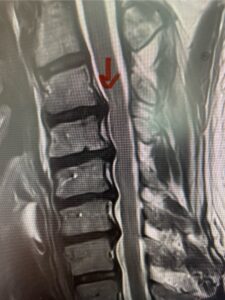

This 61-year-old female with a history of severe osteoporosis and a prior history of a laminectomy from l2-S1 with an L5-S1 instrumented fusion, presents with progressive low back pain and right lower extremity radiculopathy. MRI revealed a grade 1 L2-3 spondylolisthesis with severe stenosis mainly from severe right L2-3 facet joint hypertrophy which was compressing the right L3 descending nerve root. (Fig. 1). She had failed conservative management consisting of physical therapy and pain management with epidurals. She underwent an L1-3 revision laminectomy where we had to dissect a plane underneath the inferior aspect of the L2 lamina. We performed an instrumented fusion at L2-3 with special hydroxyapatite-coated screws to improve fixation to surrounding bone given here severe osteoporosis (Fig. 2) This worked out well and the patient had an uneventful recovery with relief of her leg pain.

Figures 1a: Sagittal and axial T2-weighted lumbar MRIs demonstrating a grade 1 L2-3 spondylolisthesis (red arrow) with severe stenosis secondary to right L2-3 facet hypertrophy (red arrow).